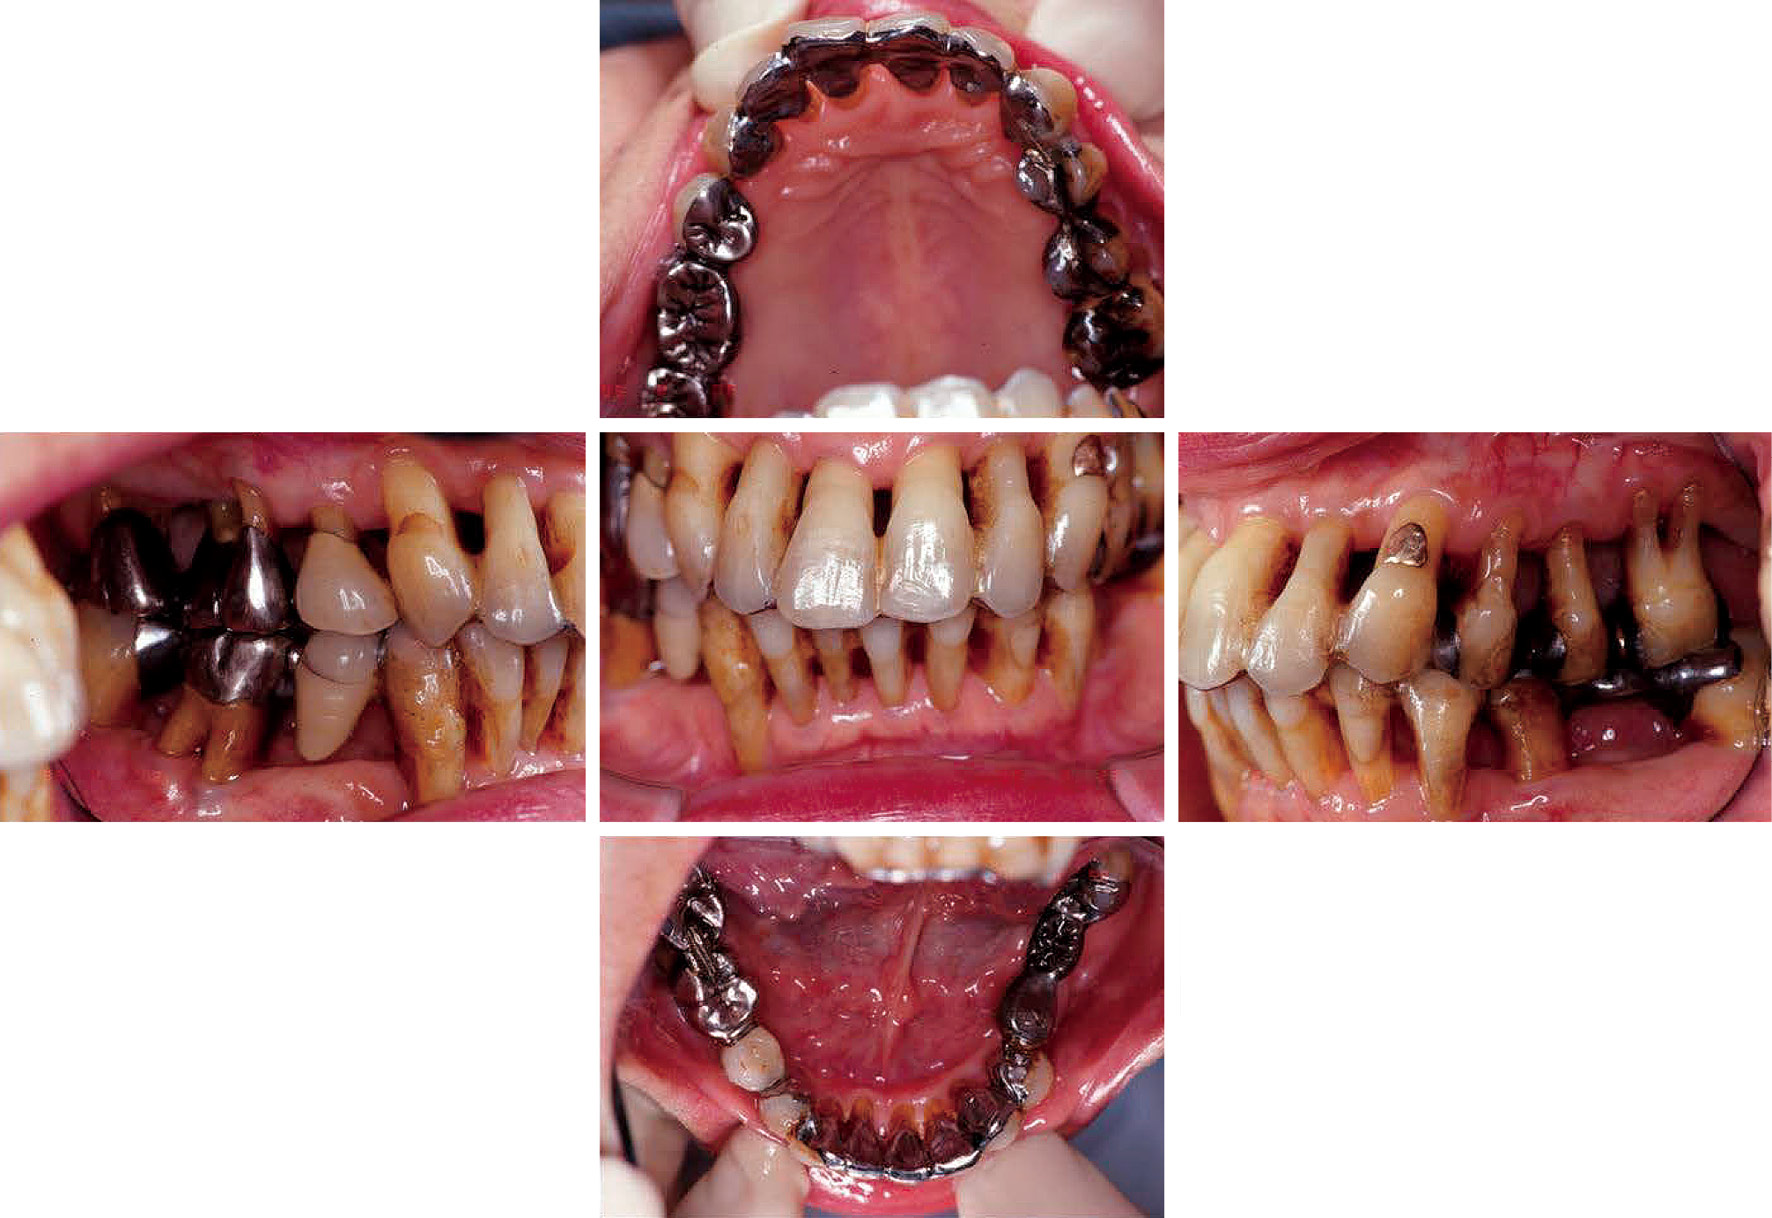

SPT2年後の病態写真(図10)およびエックス線像(図11)である。歯槽骨のいっそうの再生と骨全体の安定化傾向が認められる。

SPT 17年後の病態写真(図12)およびエックス線像(図13)である。筆者が他大学に異動する前のリコール時に撮影したものである。一月に一回の予約をほぼ20年もの間継続されたこの患者こそモチベーションの鏡として賞賛されるに値する患者であると信じてやまない。

再度目を凝らしてSPTの両群を見比べて頂きたい。15年の時間差の中で,歯槽骨が再生・回復している部位の歯肉はどうなっているだろうか。健全な組織図の通り,歯槽骨の変化に応じて歯肉自体も好ましい変化を遂げていることが理解できるであろう。長い年月をかけて,まるでクリーピングアタッチメントと同じような機構で成長しているかのような感じがする。成功の条件は完璧なプラークコントロールと高いモチベーションの継続にあることを教えてくれているようである。

SPT2年後の口腔内写真。

SPT2年後のエックス線写真。

SPT17年後の口腔内写真。

SPT17年後のエックス線写真。